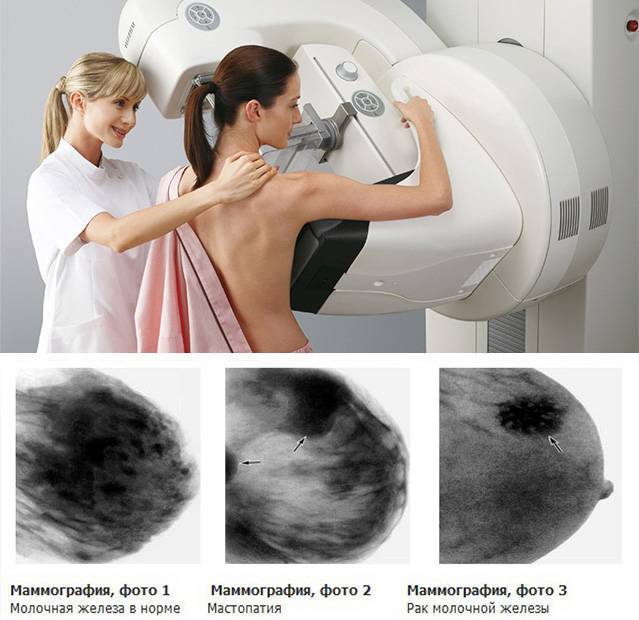

Аномалии молочной железы: медицинские примеры и визуализация

Раздел: Мудрость в деталях